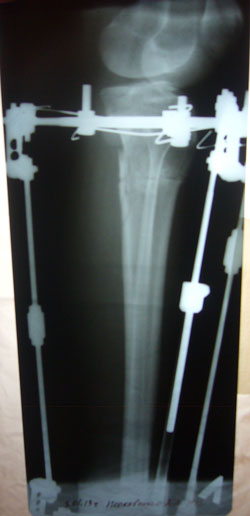

- Диагноз: О-образная деформация ног

- Дата операции.: 01.11.2012

Дата операции 01.11.2012г.

рентгеновские снимки от 03.01.2013г.

2 месяца с момента операции.